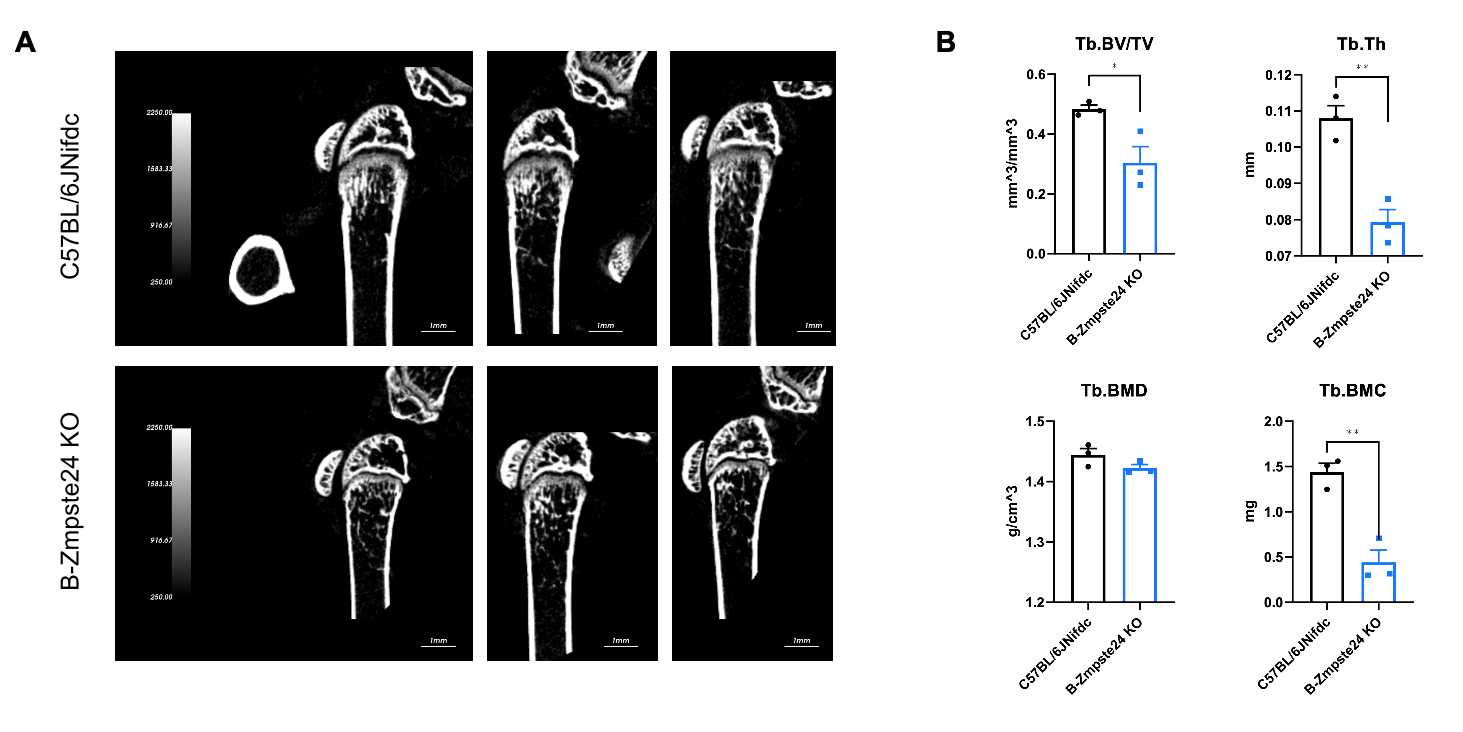

Micro-CT analysis of bone microarchitecture in homozygous B-Zmpste24 KO mice. (A) Representative micro-CT images of trabecular bone from wild-type C57BL/6JNifdc mice (n=3, male, 6-week-old) and homozygous B-Zmpste24 KO mice (n=3, male, 6-week-old). (B) Quantitative analysis of bone volume fraction (Tb.BV/TV), trabecular thickness (Tb.Th), trabecular bone mineral density (Tb.BMD) and trabecular bone mineral content (Tb.BMC). Tb.BV/TV, Tb.Th, Tb.BMC decreased in homozygous B-Zmpste24 KO mice compared with wild-type mice, indicating a deterioration or loss of trabecular bone structure, which is consistent with characteristics of osteoporosis. Data are presented as mean ± SEM. *P < 0.05, **P < 0.01, ***P < 0.001.